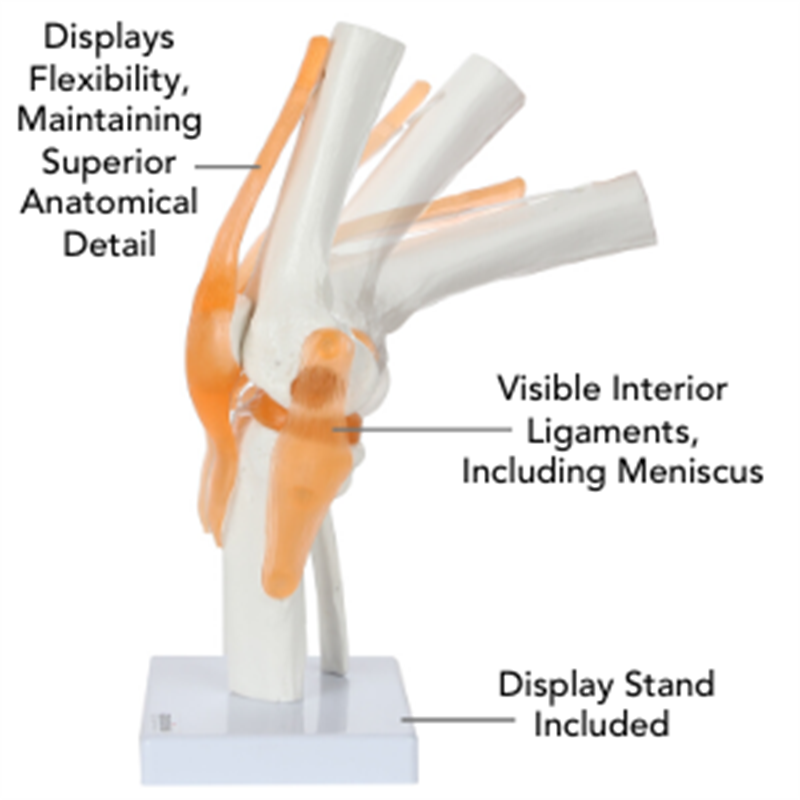

An anatomical medical model of a human knee and ligaments

An anatomical medical model of a human knee and ligaments

1. Life-size human skeleton model: The knee joint model can be bent to show anteroposterior ligaments, including the bones of the patella. Our knee joint model provides special learning assistance for anyone who wants to study knee motion

This fully functional anatomical model of the human knee provides a special learning aid for anyone wishing to study knee movement. The model can be bent to show the anterior and posterior ligaments, as well as expose the patella. Its design features a flexible rope that is completely invisible to the hardware, allowing an uninterrupted view of the knee and its ligaments. The model is firmly mounted on an attractive base. Designed by and for medical professionals, the range uses only the best materials to make each model.

Full-size anatomical model of a human knee.

The knee joint model has limited flexibility, flexible plastic ligaments and invisible hardware.

Mount on secure base for display and demonstration.

Full-color product manuals and educational guide manuals, including:

Marked with "Map" that Outlines the main parts of the knee knee

Cover a list of all 18 parts, including

femur

patella

Lateral meniscus

Knee joint model

Knee joint

Complete, flexible, high quality replica of the human knee.

Including display stand.